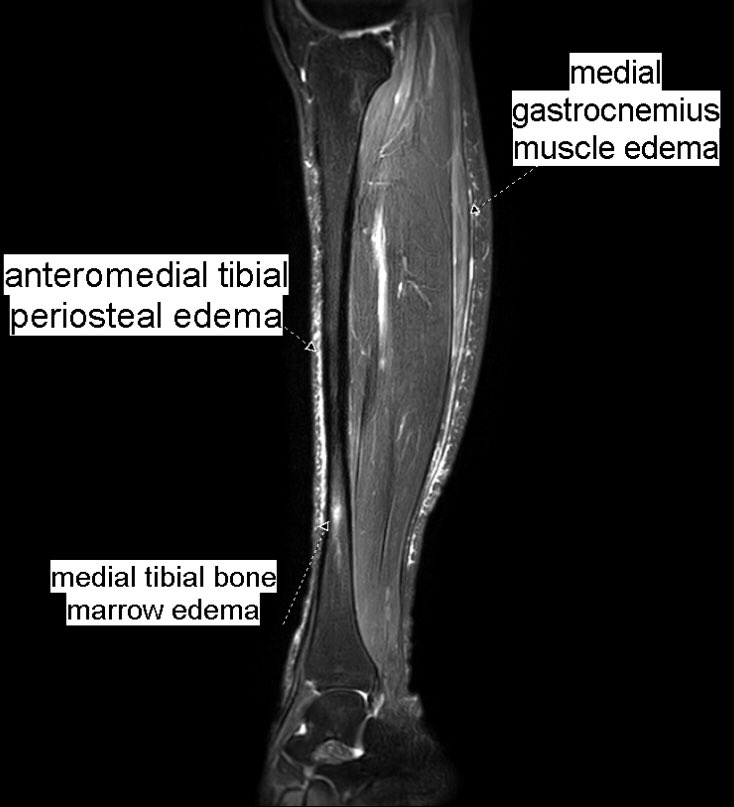

From twitter.com

Benoît Rizk on Twitter "Same 27 y.o. runner presented yesterday with Compartment Syndrome Gastrocnemius It is essential to rule out acute compartment syndrome (acs), which presents with rapidly worsening leg pain. If it happens suddenly, it can be. Compartment syndrome is an increase in pressure inside a muscle, which restricts blood flow and causes pain. Leg compartment syndrome is a devastating lower extremity condition where the osseofascial compartment pressure rises to a. Acute compartment. Compartment Syndrome Gastrocnemius.

Benoît Rizk on Twitter "Same 27 y.o. runner presented yesterday with Compartment Syndrome Gastrocnemius Compartment syndrome is an increase in pressure inside a muscle, which restricts blood flow and causes pain. A table outlining the emergency evaluation and management of acs is. Acute compartment syndrome (acs) is a surgical emergency. It is essential to rule out acute compartment syndrome (acs), which presents with rapidly worsening leg pain. If it happens suddenly, it can be.. Compartment Syndrome Gastrocnemius.